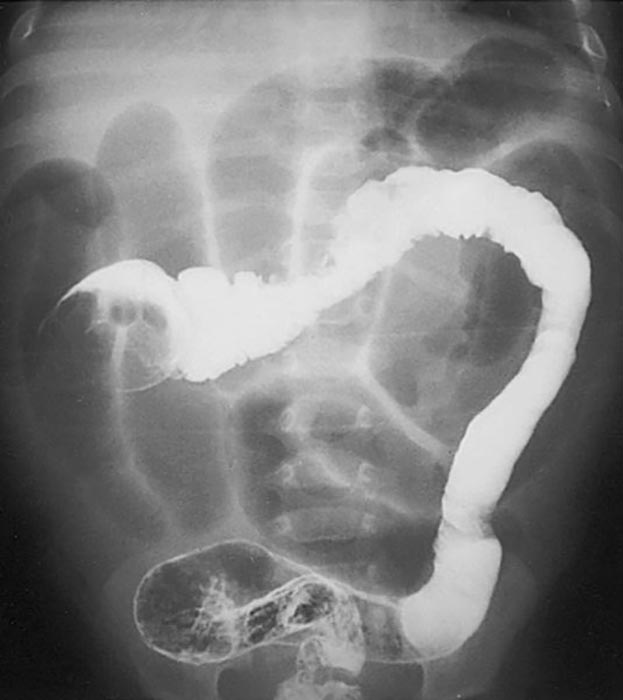

Where does volvulus most commonly occur?

In the cecum and sigmoid colon. (image shows cecal volvulvus)

How does cecal volvulus occur?

The cecum twists on its long axis and often displaces upward and to the left.

How does sigmoid volvulus occur?

The sigmoid twists on its mesenteric axis, rotating left or right.

What are the two major dangers of volvulus?

Bowel obstruction and compromised blood supply.

What can compromised blood supply lead to in volvulus?

Necrosis and gangrene.

Why can volvulus cause peritonitis?

Obstruction can cause severe distension leading to bowel perforation.

What are common symptoms of volvulus?

Severe abdominal pain, vomiting, and abdominal distension.

How is volvulus treated?

Emergency surgery to untwist the bowel.

When is bowel resection required in volvulus?

If the bowel has become necrotic.

What surgical options may be required for volvulus?

Partial colectomy, ileum reattachment, or total colectomy with ostomy.